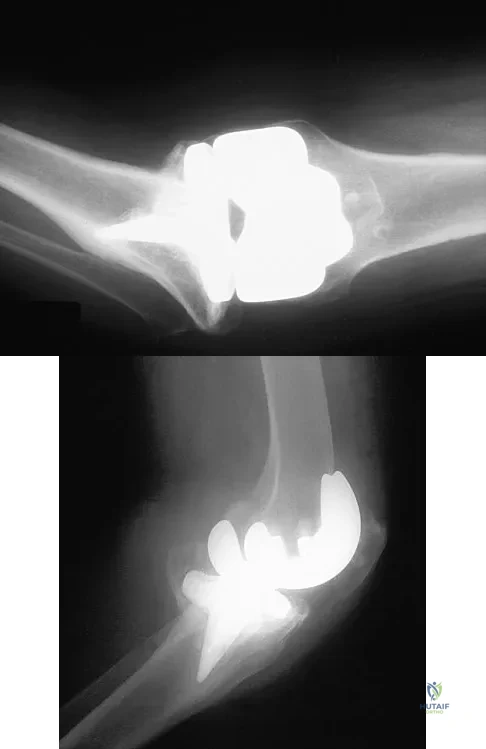

Figure 22 shows the radiograph of a 67-year-old woman who has an infected left total hip arthroplasty. The most efficient means to remove the distal cement mantle includes the use of